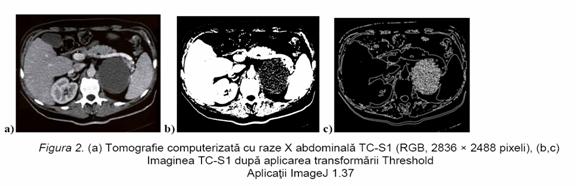

Tehnicile de procesare (prelucrare) a imaginilor contribuie la diferentierea dintre tesutul anormal (tumorile) si celelalte tesuturi, furnizand informatii detaliate cu privire structura interna a obiectului investigat intr-o mai mare masura decat imaginile tomografice neprelucrate. ImageJ 1.37 este un program Java de procesare a imaginilor. El poate afisa, edita, procesa si analiza imagini de 8-bit, 16-bit si 32-bit. Softul de prelucrare a imaginilor Adobe Photoshop CS2 a fost utilizat in conjunctie cu programul Corel PHOTO-PAINT 12.0 pentru a imbunatati calitatea imaginilor CT prin ajustarile si efectele speciale aplicate . Comanda Threshold realizeaza modificari cu privire la contrastul pixelilor reducand sau chiar eliminand elementele parazite din imagine si in acelasi timp transforma toate culorile in alb si negru pe baza valorilor originale de luminozitate ale pixelilor. Raza stabileste distanta in pixeli de la linia de contur spre interiorul suprafetelor pe care se aplica filtrul. Cu cat valoarea este mai mare, cu atat efectul de margine este mai evident. Filtrul de Egalizare a Histogramei aplicat pentru marirea contrastului controleaza intervalul de tonuri (zone sau tonuri intunecate, tonuri medii de gri si tonuri luminoase) pentru canale compuse sau separate de culoare. Ajustarea Threshold prezinta mai multe variante de executie, care au fost aplicate cu succes in studiul imaginilor CT cu raze X.